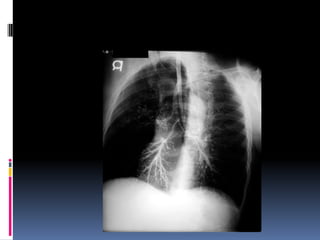

Lung fields  Infiltrates  Increased interstitial markings  Masses  Absence of normal margins  Air bronchograms  Increased vascularity

Cannon ball appearance-DDS Osteogenic sarcoma Thyroid (follicular) Testicular carcinoma Kidney Choriocarcinoma Prostate Malignant melanoma, Some GI, Some very advanced nasopharyngeal, and pharyngeal carcinomas Breast Lymphangitis carcinomatosa